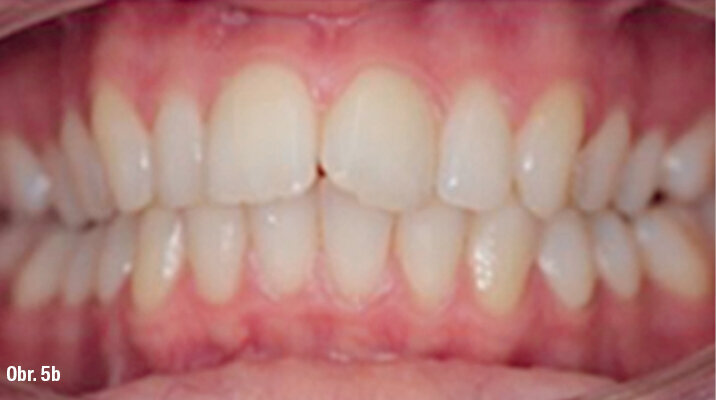

ClinCheck (Align Technology) software navrhl k získání požadovaných výsledků 63 alignerů s předepsaným množstvím atachmentů a nasazením tahů II. třídy. Odhadovaná doba léčby byla přibližně 30 měsíců. Nicméně protože se pacientka rozhodla používat přístroj AcceleDent, léčba byla ukončena již po 18 měsících bez nutnosti refinementu, tedy s původně plánovanými 63 alignery (obr. 4a–c, 5a–c).

Klinický výsledek byl vynikající, postavení molárů i špičáků v I. třídě, vyhovující překus a předkus. I profil dolní třetiny obličeje byl výrazně lepší.

Na překrytí kefalometrických snímků je zřejmá distalizace molárů o 6 mm bez výraznějšího sklonu a s ideálním bukolingválním sklonem řezáků. Tahy druhé třídy umožnily protrakci mandibuly o 1,5 mm. Jako retenční aparáty jsme zvolili Vivera retainery (Align Technology) (obr. 6, 7a–c, 8a–c).